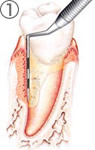

歯肉の切開

歯肉の剥離

歯根表面の清掃